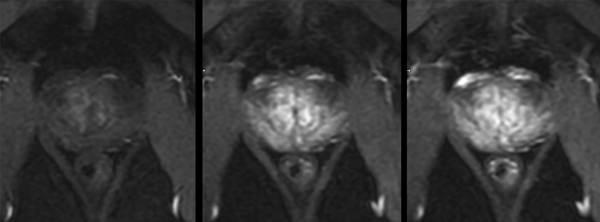

Motion-free Prostate imaging